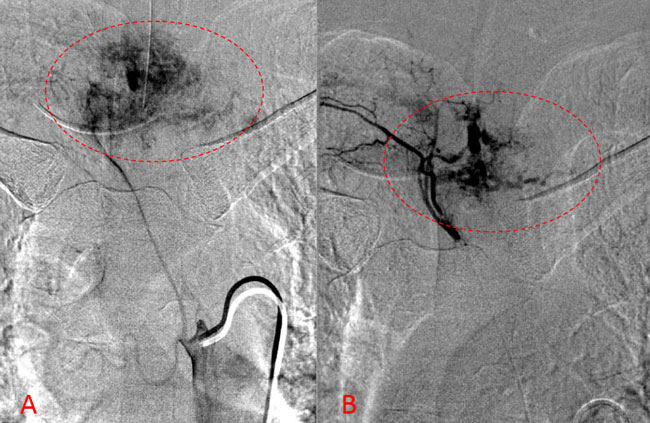

Spinal angiography showed a very hypervascular lesion fed predominantly by the right supreme intercostal artery (Figure 2. A, B).

Figure 2. (A, B) Selective angiography of the right supreme intercostal artery demonstrates extensive hypervascularity of this aggressive T3 hemangioma.

No spinal artery contributions were found to arise from this right T1-T3 pedicle. Superselective WADA testing was performed with Brevital injected through the microcatheter, which failed to elicit changes in the intraoperative monitoring, confirming safety to proceed with devascularization of this pedicle and tumor. This was performed with 100-300 micron particles achieving an excellent devascularization (Figure 3. A, B).

Figure 3. A and B) demonstrates selective PVA embolization with complete devascularization of the tumor on completed embolization.